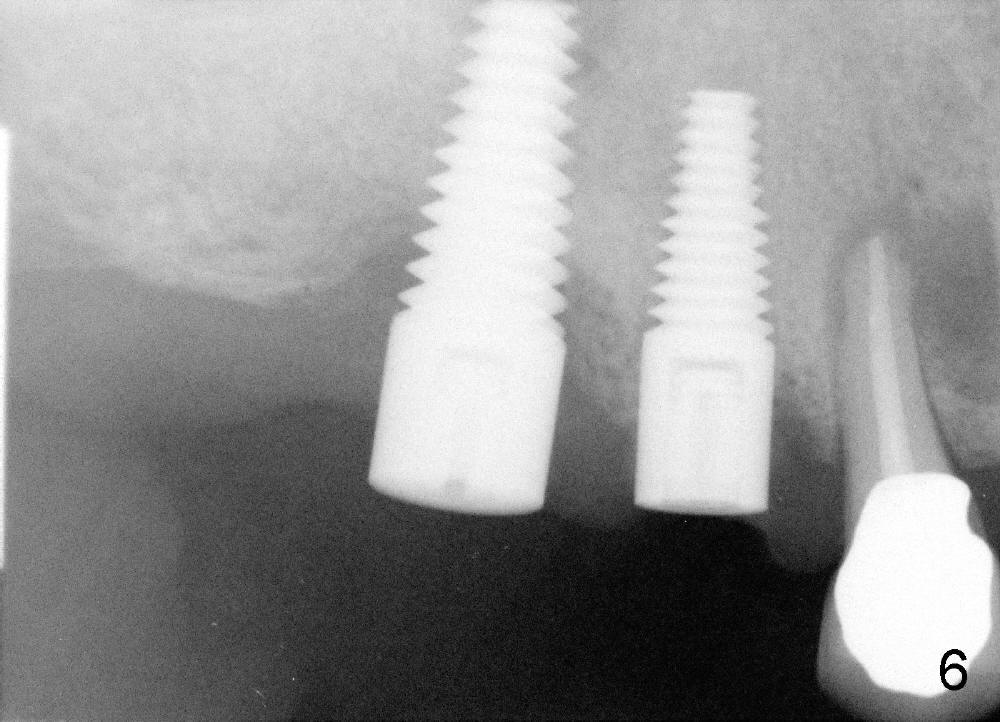

Due to finance, no treatment is provided to #5 (Fig.5 (4.5x14 mm tap),6 (4.5x14 mm implant)). PA (Fig.7) is taken 8 months postop. The crowns at the sites of #3 and 4 have been cemented for 9 months.

It appears that the crack root of #5 does not have bacteria or that there is no direct communication between #4 and 5 for bacteria to travel. The radiolucency is away from the implant site.